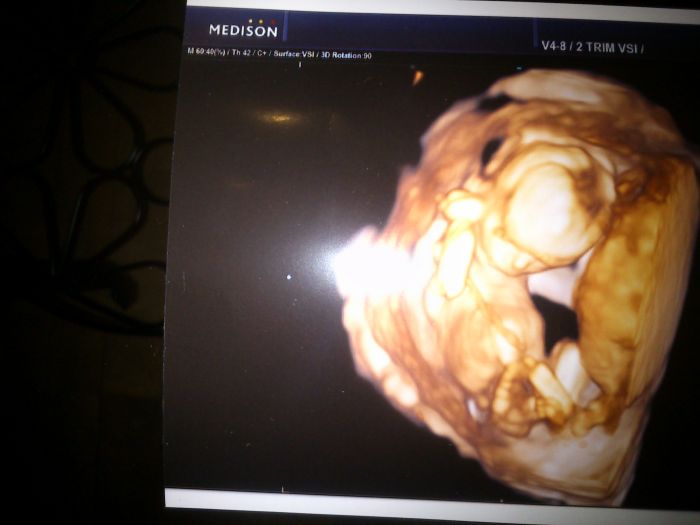

a prikladam fotecku naseho dalsiho milacka

Taky sem už konečně musím dát forku, jen je to technicky náročnější. Ale včera jsme dostali i obličej a je tak pěkně vidět :-). Tak jsme byli na genetice pěkně celá famílie

, ještěže jsme zatím jen 4. Malá měla při poslední kontrole 11 cm a teď má 22 cm! To je macek

3D utz se u nás dělá minutu, dají teda dvd a fotečku, ale stojí to tisícovku a já mám 3D při každé prohlídce teda zadarmo, protože při kontrole to berou i 3déčkem a ještě dostanu vždycky 4 fotky. Takže pro mě by bylo zbytečný dávat za to peníze. Nevím jak jinde. Ale to je na té genetice, můj. dr. mi ani utz. nedělá. A už asi až do 30tt dělat nebude.Ale nechápu, proč dělají 3D tak pozdě, vždyť už od začátku jde všechno tak pěkně vidět, a teď nám ukazoval a popisoval všechno. Obličej, ručičky, prstíky, nožičky, bříško..